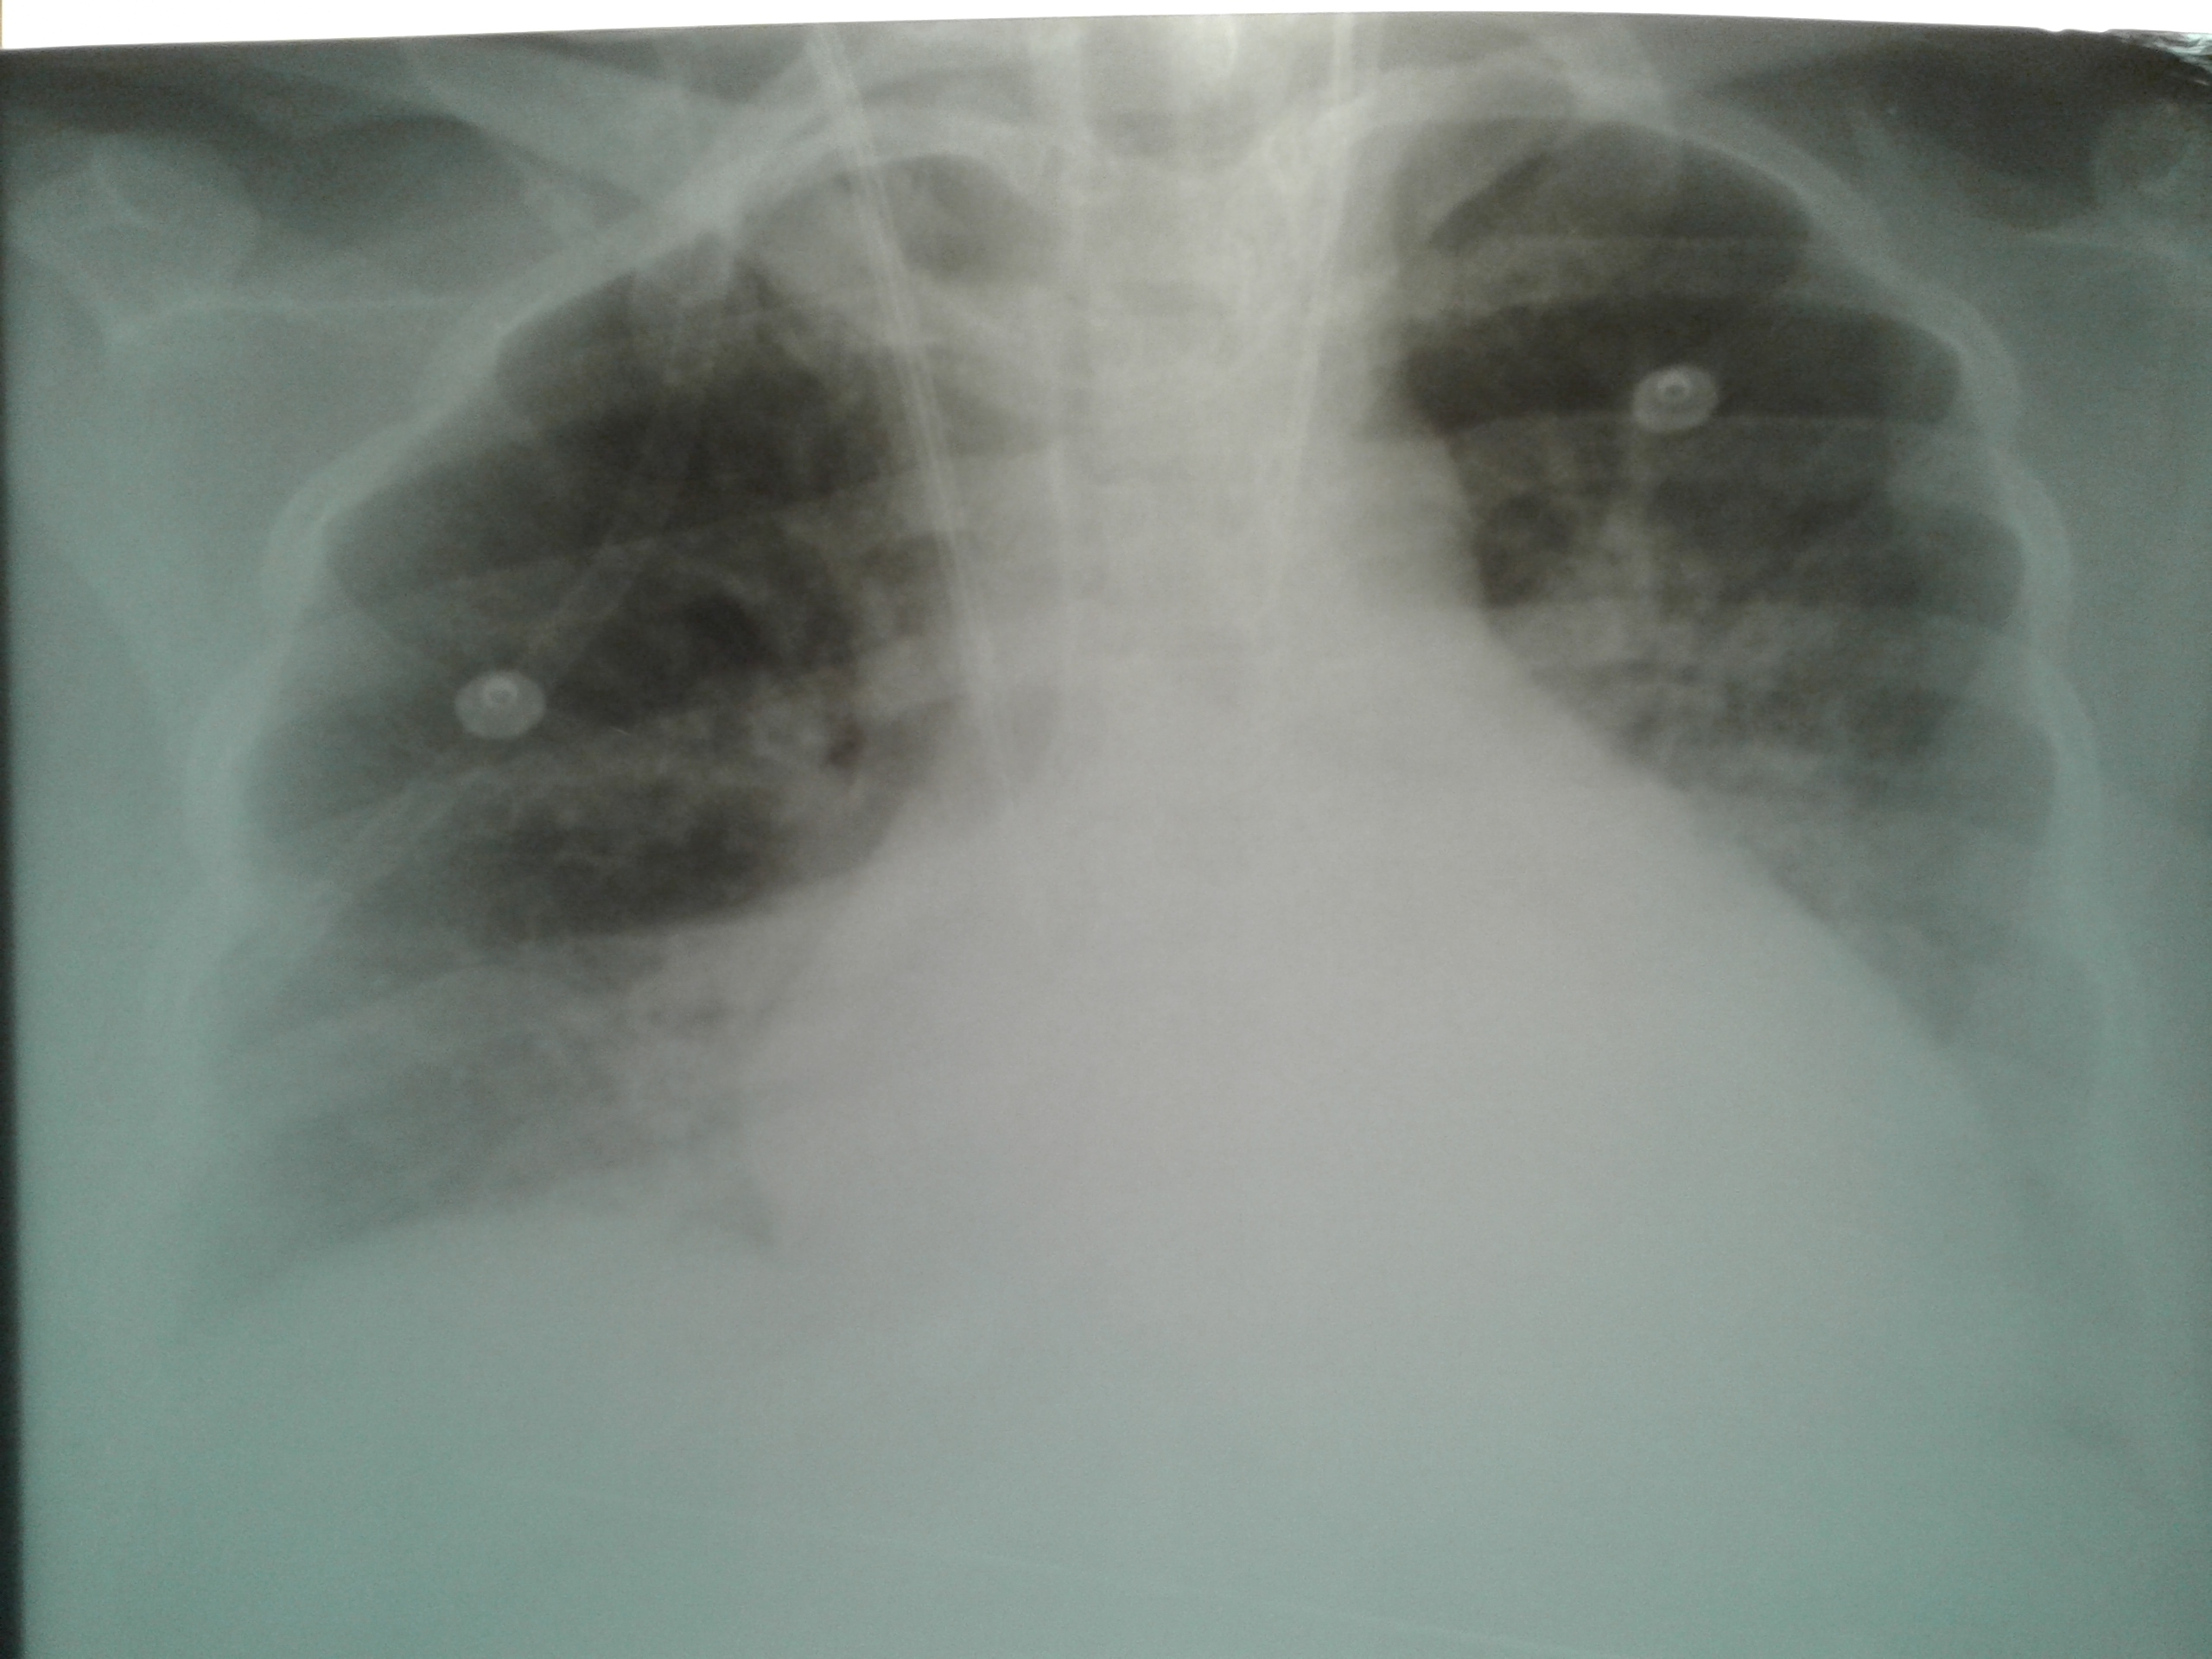

La Miocardiopatía Periparto (MCPP) es una complicación grave del embarazo y el puerperio, de elevada morbimortalidad. Su diagnóstico es de vital relevancia, debido a los índices de mortalidad materna en la provincia de La Rioja. Su verdadera prevalencia e incidencia en nuestro país se desconoce; probablemente a consecuencia de subdiagnosticos. La incidencia más alta en las poblaciones estudiadas se en cuenta registrada en Haití, donde se estima 1 caso cada 299 nacidos vivos, le siguen Sudáfrica 1 caso cada 1000 nacidos vivos y la más baja en EEUU con 1 caso cada 4000 nacidos vivos (1). Constituida por pacientes previamente sanas, sin patología cardiaca preexistente, y en edad reproductiva. En este artículo describiremos el síndrome, sus causas, fisiopatogenia y presentaremos dos casos que fueron diagnosticados y abordados terapéuticamente en la Unidad de Terapia Intensiva Obstétrica (UTIO).